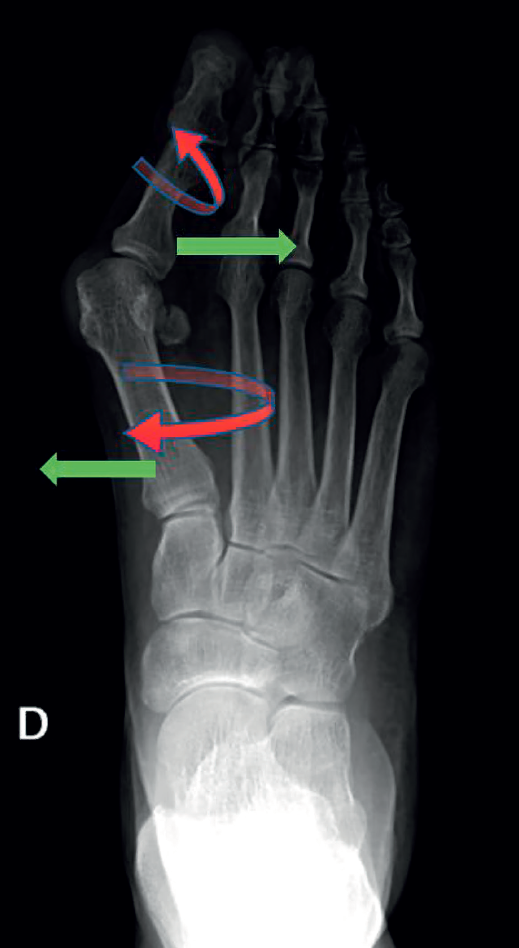

Esta técnica suele ser complementada con una osteotomía de falange proximal del primer dedo (Akin) para corregir la rotación del primer dedo. Algunos ejemplos de pacientes intervenidos en nuestro centro se recogen en la Figura 3.

Figura 3. Ejemplos de hallux valgus intervenidos en nuestro centro: A: pie izquierdo pre-intervención quirúrgica (IQ); B: pie izquierdo post-IQ; C: pie derecho pre-IQ; D: pie derecho post-IQ.